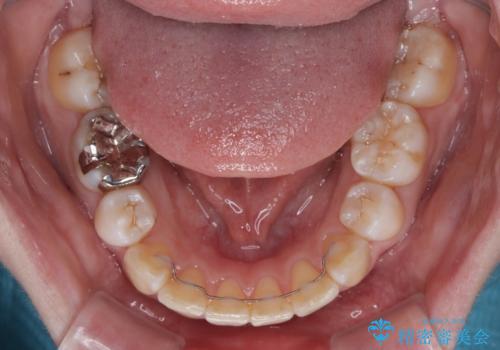

- 奥歯の欠損と、抜歯矯正の後戻りを気にして来院された患者様です。

上下前歯をワイヤー保定していましたが、強い舌の突出癖により上下ともにスペースができ、上下前歯は非接触になっていました。

また、上顎臼歯は虫歯により抜歯されてから放置されている状態でした。